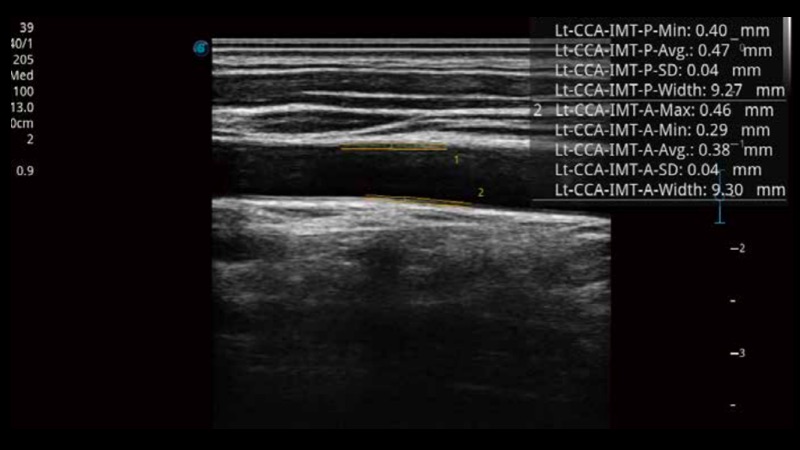

To give a quick measurement of carotid intima-media thickness ensures good reproducibility and high diagnostic efficiency.